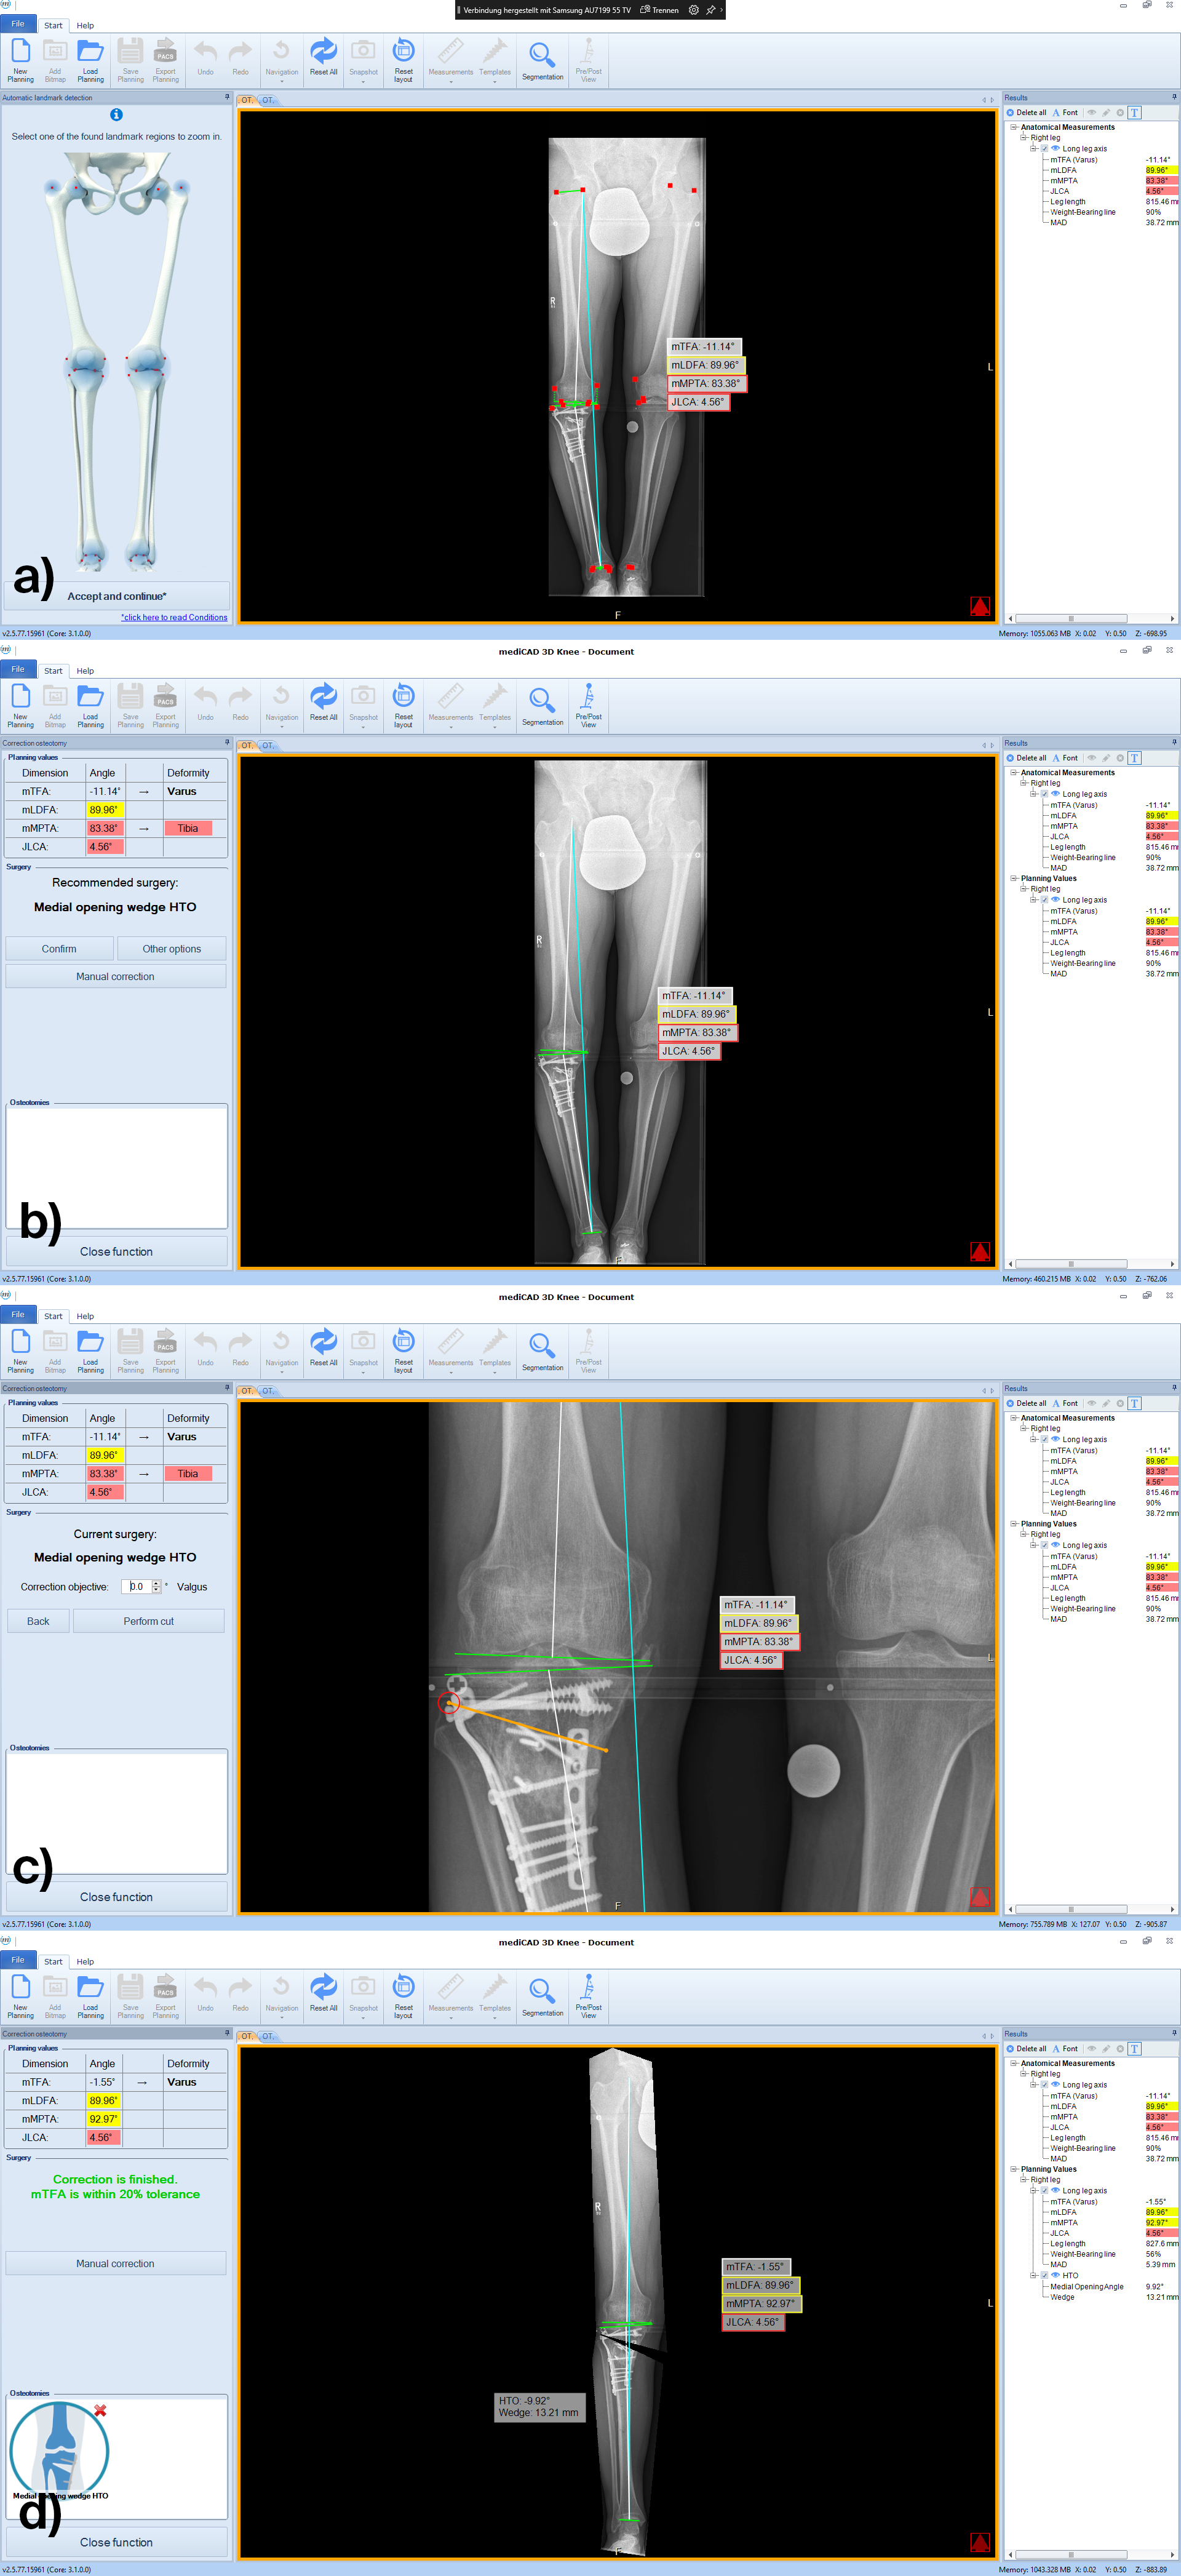

The software automatically detects all necessary landmarks (Fig 1). Based on their position (which can be adjusted manually) the software calculates all essential values (axis, joint lines, and angles) and delivers a detailed report. A traffic light system illustrates normal, intermediate, or pathological values.

Following the deformity analysis, the software automatically recommends a surgical procedure, eg, medial opening wedge high tibia osteotomy, depending on the type of deformity (Fig 2). The user can follow the proposed procedure or choose individual options.

Once the procedure is selected, the software automatically places the cutting line and hinge point for the chosen osteotomy adapted to the individual anatomical condition (Fig 3).

Next, deformity correction is visualized to the preferred new alignment. If a monofocal correction results in pathological joint angles, the implemented algorithm recommends double-level osteotomy and balance the two osteotomies between multiple constraints and normal values such as wedge heights, mechanical medial proximal tibial angle (mMPTA), mechanical lateral distal femoral angle (mLDFA), mechanical tibiofemoral angle (mTFA); (Fig 4).